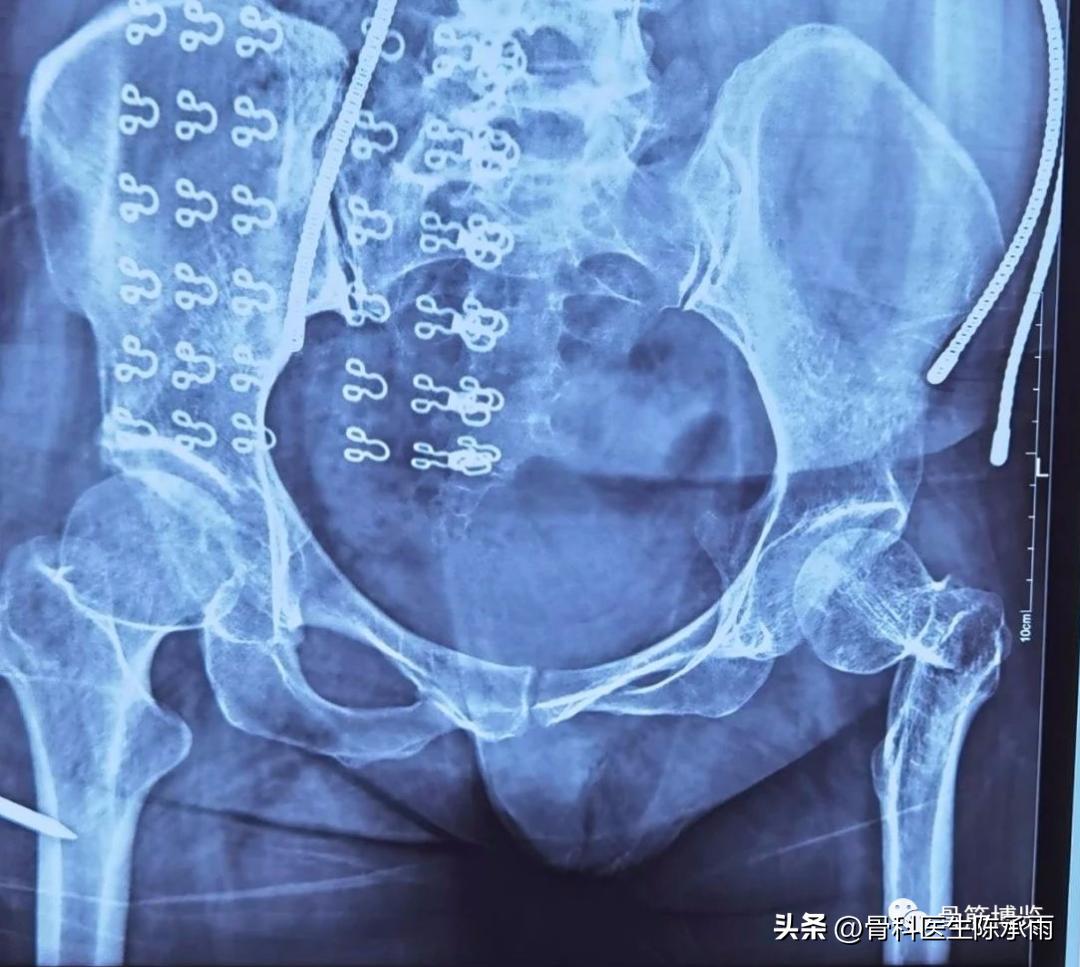

我们这例患者是一位脑瘫患者,患侧肢体短缩细小,股骨颈处及股骨髁上均做过截骨手术,失去了正常的角度,且股骨颈较细。给手术带来不小的难度。